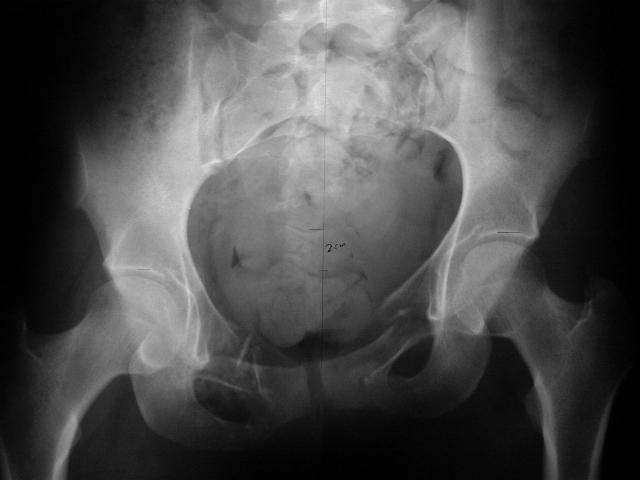

An example of our current approach to similar injuries - A 26 y.o. male admitted to us Aug 23, 2001 6 weeks after injury (compression by a wheel of a truck).

An external fixator was applied and gradual reduction was started - lateral traction to mobilize sacral fracture and then the hemipelvis was moved downward. Then lateral compression was performed. Yesterday iliosacral screws was inserted.

The last couple of images are skewed, they were made in OR and patient was not properly positioned.